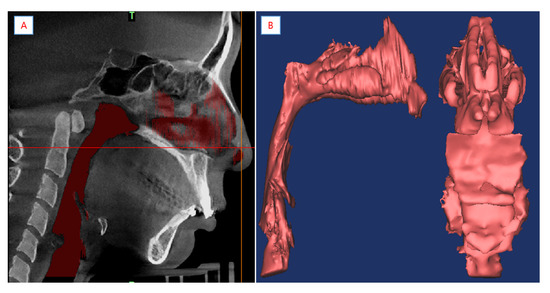

2.3. Reconstruction of the Model and Mesh Generation

The 3D-DOCTOR software was used for the reconstruction of the airway models for all patients. About 600 images of the upper airway were segmented with a threshold value between −1024 to −480 Hounsfield units. Figure 5 shows the anatomy of the upper airway, which has the smallest area. Given the complexity of the morphological characteristics of the upper airway, setting the fluid domain is vital for analysis. As anatomy can significantly change the facial features of people, an understanding of the interior anatomy of humans can solve this problem. The highest number of obstruction sites detected by studies were at the level of the oropharynx [21]. A collapse occurs close to the velopharynx or oropharynx. The total fluid domain was set from the nasal vestibule to the laryngopharynx. Using the CT data, the modeling process was subsequently executed using the following steps. First, the extracted boundary was set on the CT images. Then, the boundary piles on the CT images were laminated, and finally, the model created through the lamination was cleaned and saved in stereolithography (STL) format. It should be noted that numerous other methods can be used for creating models in commercial programs. Anatomically accurate 3D models were converted to the STL format (Figure 5 and Figure 6). The STL files were then imported to the integrated computer engineering and manufacturing code for CFD (ICEM-CFD). Meshing was performed on the prism and tetrahedral meshes generated by ICEM-CFD. The meshing elements and nodes were taken from pre-operation cases at 1.21 × 106 and 6.25 × 106, and post-operation cases at 1.90 × 106 and 6.89 × 106, respectively. The finite volume approaches of the cells’ near-wall boundary were irregular, which may require tailored treatment. The prisms can first create a layer of regular prisms near the wall and then mesh the remaining volume with tetrahedrons. This grid approach gives better solutions and convergence of computation [22]. A grid invariant study was performed to check the grid independence of the simulation meshes. This compared three different meshes (fine: 1.67 × 107 meshes; mild: 8.16 × 106 meshes; and coarse: 4.6 × 106 meshes) for the pre-operative patient 5 model. In terms of average velocity at the minimal cross-sectional area, the coarse case and mild case had a disparity of 2.65% and the disparity within the mild case and fine case was 2.27%. Thus, the meshes in the moderate case proved to be satisfactory for describing the airflow dynamics of the upper airway.

Figure 5. (A) Segmented pharyngeal airway. (B) Anatomical 3D model of pharyngeal airway was created using CBCT.

Figure 6. Superimposition of the pre- and post-pharyngeal airway model.